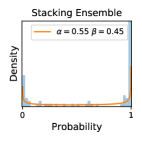

5.1 Distribution of Uncertainty Scores

Distribution of Uncertainty Scores Across Different Severity Levels As explained in Section 3, each uncertainty metric essentially defines an order/ranking among the data points. We conducted an analysis to better understand what data will be assigned high uncertainty under a particular uncertainty metric . Picking out the highest ranked data points (), we calculated the ratio of data points from each SL. Figure 4 summarizes the results as box plots for the Kaggle-DR and the Messidor-2 datasets; additional detailed statistics can be found in Table S.1 in the supplementary materials. From the plot and table, SL1 & SL2 examples account for a higher proportion among the top-ranked uncertain examples across the three ensemble methods. This finding matches our intuition that incipient disease examples (SL1 & SL2) are more likely to be considered uncertain by ensemble methods due to their ambiguity.

Comparing the three ensemble methods in Figure 4, the stacking ensemble method has the highest ratios of SL1 & SL2 data among the high-uncertainty examples it identified under both mean and var. TTA showed slightly better performance than MC-dropout but still falls behind the stacking ensemble method. Considering the fact that SL0 examples accounted for the majority of the dataset, the stacking ensemble method was much more precise (specific) in selecting truly ambiguous data points that were difficult to classify. From Figure 3, we can also see that the stacking ensemble method greatly outperformed the other two methods in finding false negatives under both mean and var uncertainty metrics.

In contrast, the MC-dropout method showed the worst overall performance among the three, as it can be seen from the high ratios of SL0 examples among the uncertain negatives in Figure 4. The histograms in Figure 2 provides another perspective to look into the phenomenon, where a decent proportion of MC-dropout model’s predictions on SL0 inputs entailed low confidence (far from 0 or 1), which from another angle explained why MC-dropout was less specific in terms of lower FNP; many no-DR inputs (i.e. SL0) were erroneously assigned high uncertainty by MC-dropout models.

It is still an open question why the evaluated MC-dropout networks signaled relatively high uncertainty on SL0 & SL3 & SL4 data that are less likely to be ambiguous. We conjecture that much of the “uncertainty” indicated by disagreement among test-time dropout samples actually reflects the stochastic nature of dropout networks rather than the real decision uncertainty associated with the data. It is worth noting that the MC-dropout model we evaluated was not weak per se; they all achieved above Area Under Curve (AUC) scores on test sets. The weakness of individual test-time samples (which explains their low-confidence predictions on SL0 & SL3 & SL4) might have been hidden when they are aggregated into an ensemble—a well-known advantage of ensemble learning. Our results suggested that the uncertainty information given by implicit ensemble methods such as MC-dropout and TTA might not be as reliable as that from explicit ensemble approaches (e.g., stacking ensembles). Similar findings on MC-dropout can be found in some previous papers [1].